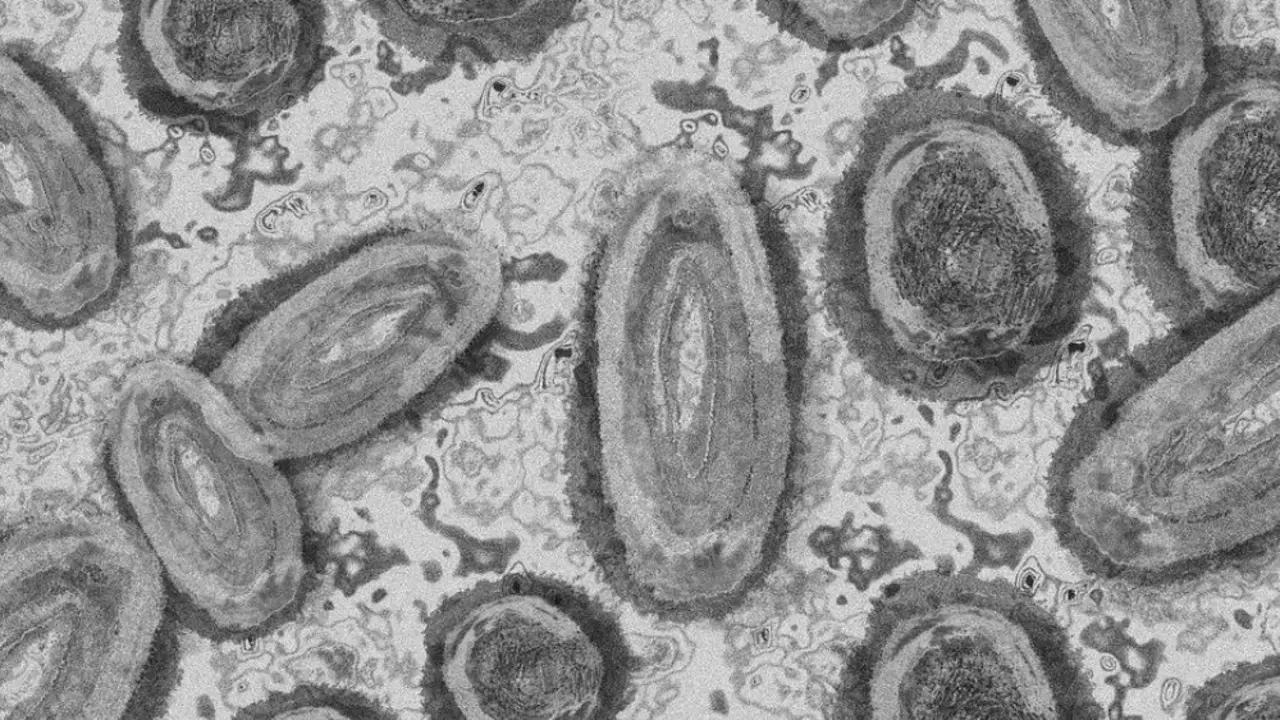

Lanzarote registra su primer caso de la viruela del mono Hasta ahora hay 134 casos confirmados, de los que 82 se detectaron en Gran Canaria, 46 en Tenerife, cuatro en Fuerteventura, uno en La Palma y otro… biosferamedia

Tres casos sospechosos en estudio de la viruela del mono en Lanzarote Desde el inicio de la alerta, Canarias contabiliza 118 positivos y once casos en estudio, de los que cinco son probables y seis sospechosos biosferamedia

Canarias llega al centenar de casos de la viruela del mono, ninguno detectado en Lanzarote Todos los casos activos están teniendo sintomatología leve y permanecen en aislamiento domiciliario recibiendo seguimiento por parte de Atención… biosferadigital

Cuatro nuevos casos de viruela del mono Desde el inicio de la alerta, Canarias registra 45 positivos y cinco en estudio, de los que cuatro casos son probables y uno sospechoso biosferamedia